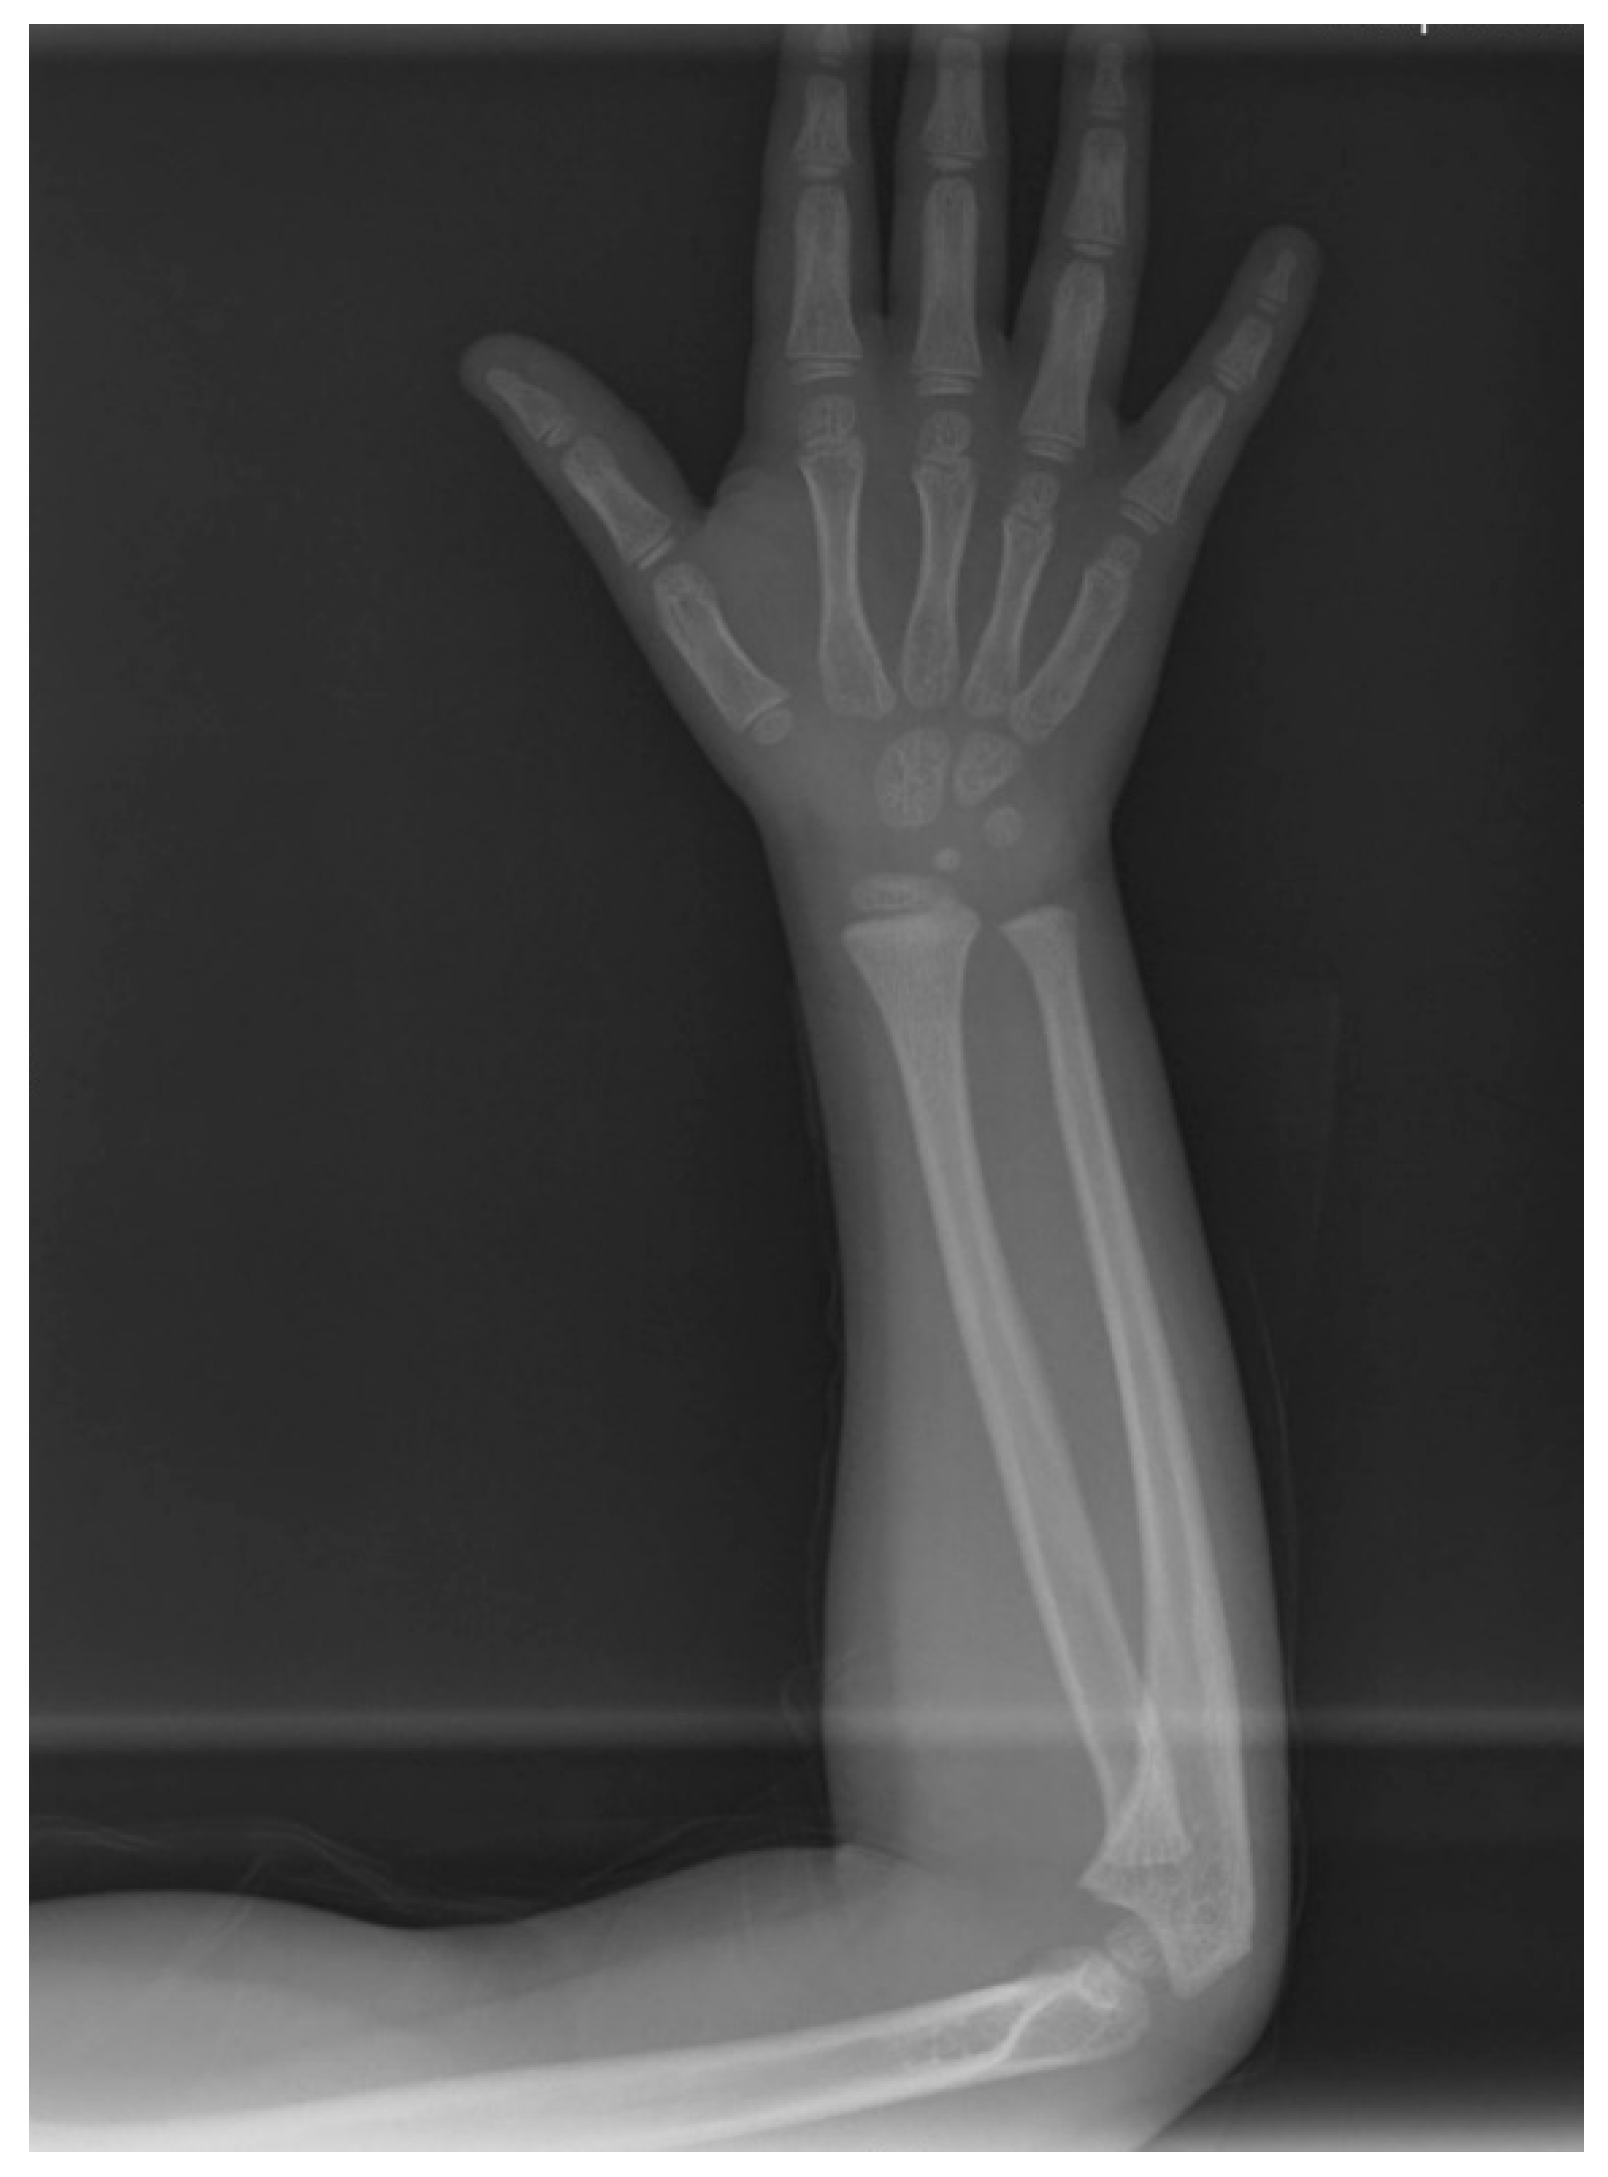

Figure 3.

Hand-wrist and long bone radiographic presentation of the daughter exhibiting no osseous defects.

The pre-treatment panoramic radiograph revealed short root length of most of the teeth, delayed tooth eruption, obliteration of pulp chambers and periapical radio-lucencies, not associated with periodontal disease or pulp inflammation. Horizontal crescent-shaped lines along the cementoenamel junction were evident in several teeth. Based on radiographic characteristics, this patient was subclassified as DD-Ic [10]. The permanent maxillary canines were impacted (Figure 1). Pre-treatment cone-beam-computed-tomography scans showed that the upper right maxillary canine (#13) was labially impacted; the contralateral canine (#23) displayed a more palatal position. Both teeth were above the roots of the adjacent lateral incisors, in close proximity to them and to the roots of the central incisors (Figure 2). Sclerosis of the maxilla and the mandible was absent in this case, as well as in the skeleton (Figure 3).

In the present case, the diagnosis was based on the clinical and radiographic findings, as well as on the patient’s and family dental history. Dentin defects are classified into Dentinogenesis Imperfectas (DIs, types I–III) and Dentin Dysplasias (DDs, types I, II) [27,28]. Radiographically, it resembles the phenotype of DD-I; narrow roots and small or obliterated pulp chambers and root canals are common findings. Teeth appear blue-gray or amber brown and opalescent, characteristics that were not evident in our case. DI type I is also accompanied by osteogenesis imperfecta, a disorder of bone fragility, and DI type II by hearing loss [27,28]. The present patient exhibited neither bone/hearing defects according to her medical history nor any of the clinical dental characteristics of DI. Therefore, this entity was excluded from the differential diagnosis.

Type I collagen forms the organic phase of the dentin [27]. Most cases of osteogenesis imperfecta are associated with mutations in the procollagen type I genes COL1A1 and COL1A2, leading to abnormal collagen I fibrils formation [32]. However, the clinical characteristics of osteogenesis imperfecta do not resemble these of the present case.